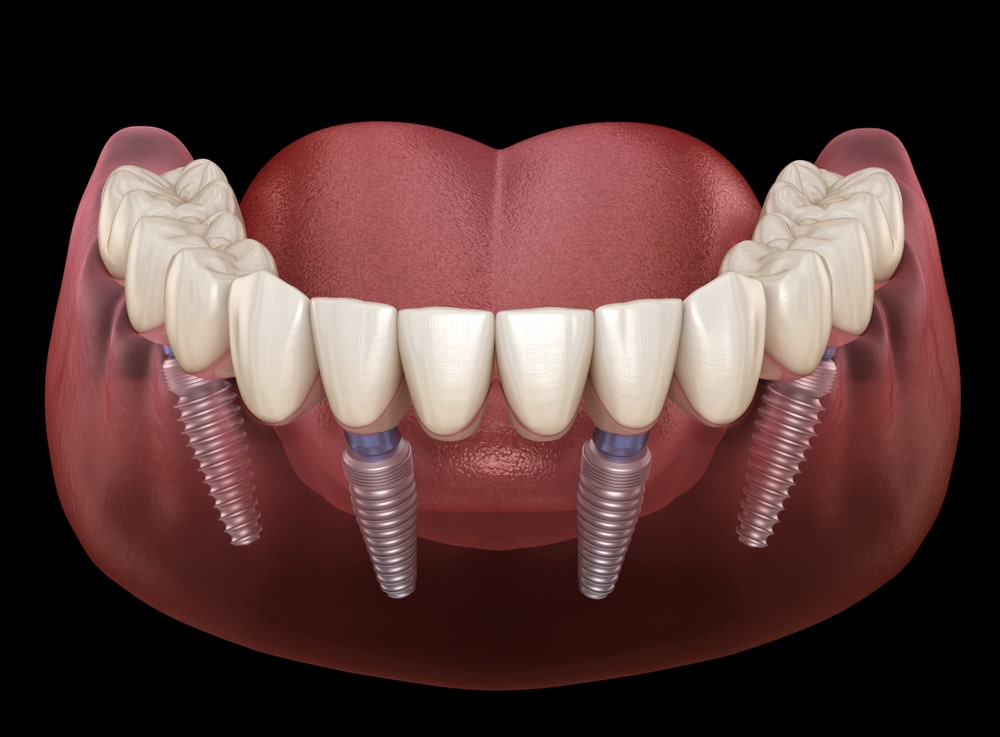

無論是固定式假牙All on 4、All on 6,使用單顎4支/6支植體做為人工牙根,固定於牙床上,藉由拱橋力學設計原理,平均分散植體力量去支撐整排假牙。因此,固定式植牙最接近自然牙的假牙形式,唔單單穩定性高、咬合力佳,亦沒有活動式假牙的異物感。

配合一日全口重建療程,當日手術後,裝上臨時假牙,即可有牙恢復咬合力。